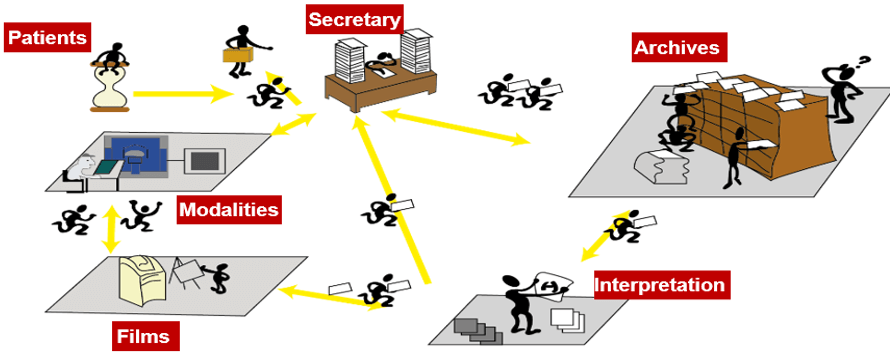

In the years before 2008, most departments in the country used the same charting system. It was a system of charts, forms, and cubbies. The charts were moved from one cubbie to the next, from the nurses and doctors to the medical secretaries.

The daily struggle in imaging was to find your patient’s previous reports or films, review any information that had been updated on the patient in their chart and prepare images for the radiologist to compare. More time was spent finding the previous images than caring for patients. We have now progressed to electronic records making the lives of all health care professionals much easier. This has made a huge impact on medical imaging.

The work organization before the RIS- PACS integration: